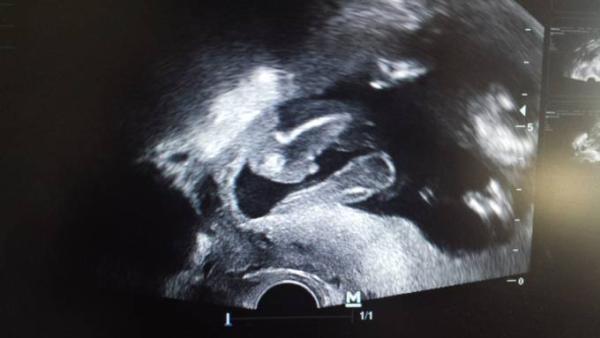

Wir bekommen einen Jungen Ich hab mich auch total gefreut wobei ich mir ja schon eine kleine Theresa gewünscht habe ;)

Mein Mann typisch sagt das er nie gezweifelt hat das es ein Junge wird

Da hatte ich ja Glück war nicht mal ein regulärer Schall, aber meine Frauenärztin schaut immer kurz ob das Herz schlägt wo die Plazenta ist (meine sitzt etwas tief, kann sich aber noch geben) und da hab ich sie gefragt ob sie es sehen kann und dann hat sie es gleich gefunden